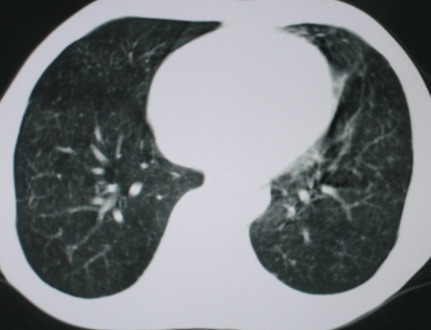

以下是引用医影拾贝在2008-6-3 18:48:00的发言:[br]双上肺弥漫性小结节影,纵隔窗内钙化淋巴结影,考虑血播性tb可能性较大,不除外肺ca可能

以下是引用卜一在2008-6-3 19:33:00的发言:[br]双肺结节,以双上肺分布为多,期间搀杂片状致密影及索条致密影。考虑:继发性肺结核伴血型播散可能性大。不除外肺泡ca的可能!另:椎体退变!

以下是引用panyishengct在2008-6-3 21:09:00的发言:[br]双上肺弥漫性小结节影,纵隔窗内钙化淋巴结影,考虑矽肺或/和tb可能性较大,不除外肺ca可能。腰椎考虑退变。 [br][br]